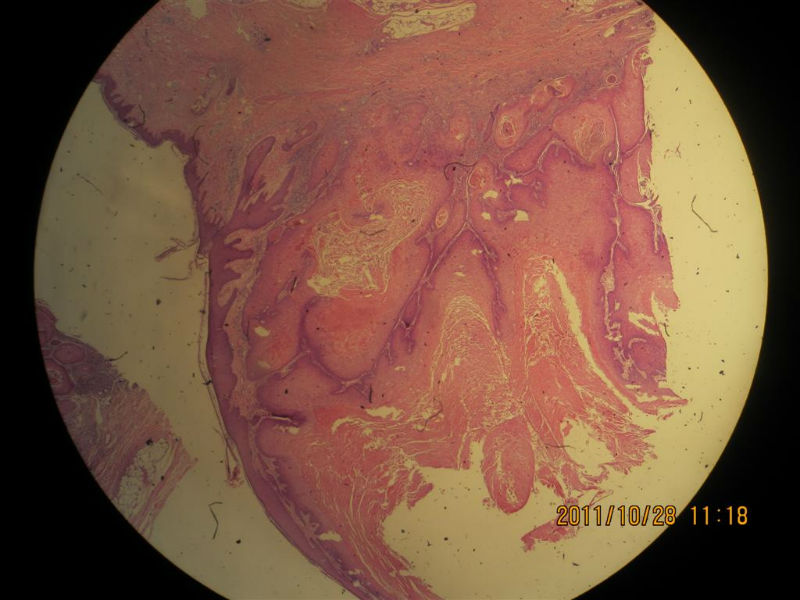

女性,71岁,右前臂肿物。角化棘皮瘤还是高分化鳞癌?

• 女性,71岁,右前臂肿物。角化棘皮瘤还是高分化鳞癌?图1

图1

不知道肿物的生长速度怎样?活动度?低倍看火盆样外观、唇样边缘,底部较平整,无明显突破。更趋向于角化角化棘皮瘤。

低倍镜见表皮呈火山口样,内充满角质团块,周边上皮增生呈衣领样,底部表皮增生呈假上皮瘤样,上皮角不规则延伸至真皮,真皮大量炎细胞浸润.

低倍镜下看符合角化棘皮瘤